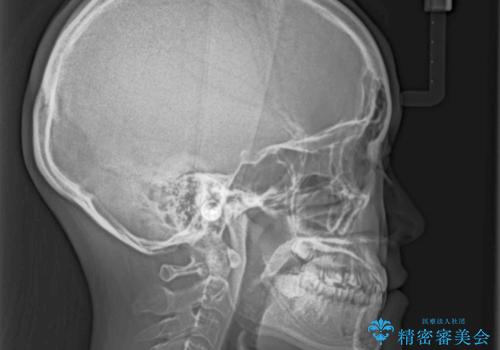

奥歯の反対咬合 上顎骨を拡大してインビザラインで矯正

- 奥歯の反対咬合を気にして来院された患者様です。

反対咬合は上顎骨の幅が下顎骨よりも小さいことが原因なので、拡大装置により骨幅を広げて上下関係を改善し、その後インビザラインにて歯並びを整えることとしました。

反対咬合が改善され、食いしばり癖もなくなり、顎関節の負担が軽減されました。

上顎骨を拡大したことで前歯に隙間ができ、1ヶ月ほど恥ずかしい時期がありましたが、しっかりとした咬み合わせに仕上がり、患者様には大変満足していただきました。